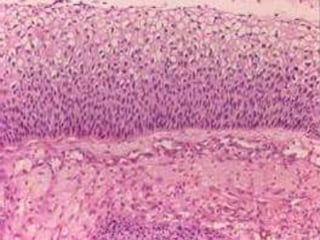

Carcinoma epidermoide in situ

• 15.